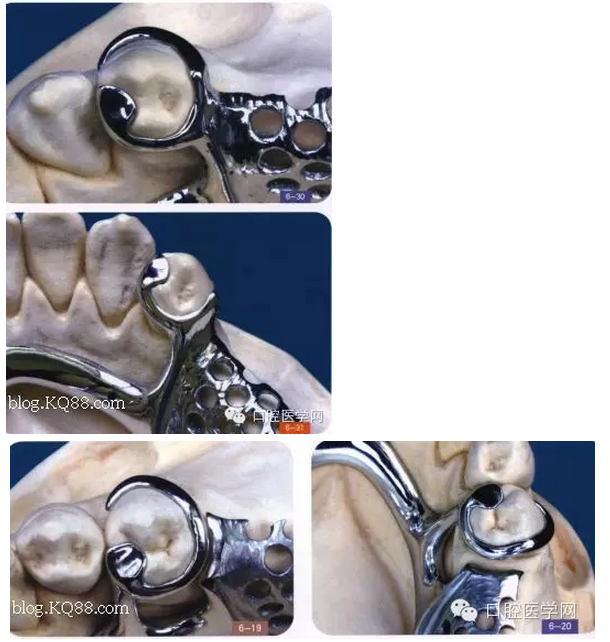

其實RPI,RPA卡換組對于后牙游離缺失在臨床中很常用,CPI卡換組由三部分組成,近中和支托,遠中臨面板,和頰側(cè)I桿組成,近中和支托起一個應力中斷作用,能有效預防近中基牙扭轉(zhuǎn)

1是近中合支托,2是臨面板,3是I桿

CPI卡環(huán)應用于遠中游離缺失,近中基牙不健康的基牙,當遠中產(chǎn)生一個向黏膜處的壓力時,把力量通過近中和支托,傳寄給基牙,而不是直接在遠中處直接傳給給基牙,這樣就產(chǎn)生了一個應力中斷作用能有效保護基牙,同時頰側(cè)和遠中的I桿和臨面板下沉,滑動,能有效預防基牙扭轉(zhuǎn),同時I型卡環(huán)與基牙的接觸面積比較小能防止食物存留預防繼發(fā)齲但是有一前提:游離缺失處,牙槽脊條件比較好,對于牙槽脊條件差者,要設(shè)計遠中合支托,如果頰側(cè)牙體倒凹大,口腔前庭小于5mm者要設(shè)計CPA卡換組(以下圖片來自中醫(yī)大)

(CPA及變異CPA卡環(huán)組)